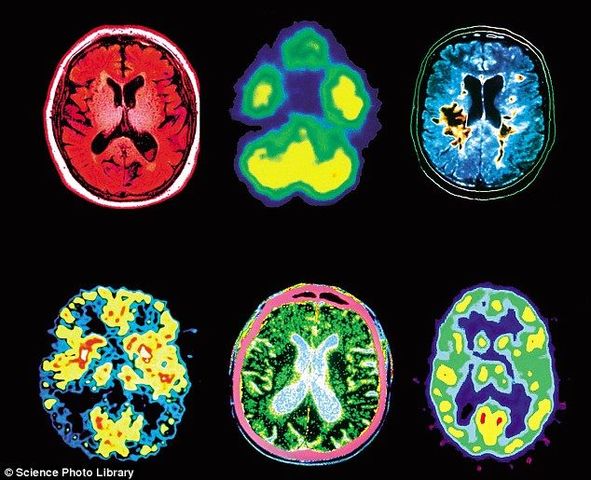

There are two main types of Neuroimaging techniques and they are Structural and Functional. Structural Neuroimaging includes CT scans and MRI's and Functional Neuroimaging includes PET scans and fMRI's.

• Structural and Functional Neuroimaging

Structural and Functional Neuroimaging

Structural:

CT scans- Computerised Temography, takes x-rays of the brain at different angles, able to locate tumors and strokes.

MRI- Magnetic Reasoning Imaging, able to show very fine tissue in detail, diagnoses structural abnormalities. Functional:

PET- Position Emission Tomography, shows brain function, measures brain activity.

fMRI- Functional MRI, measures brain activity, records levels of activity in different parts of the brain.